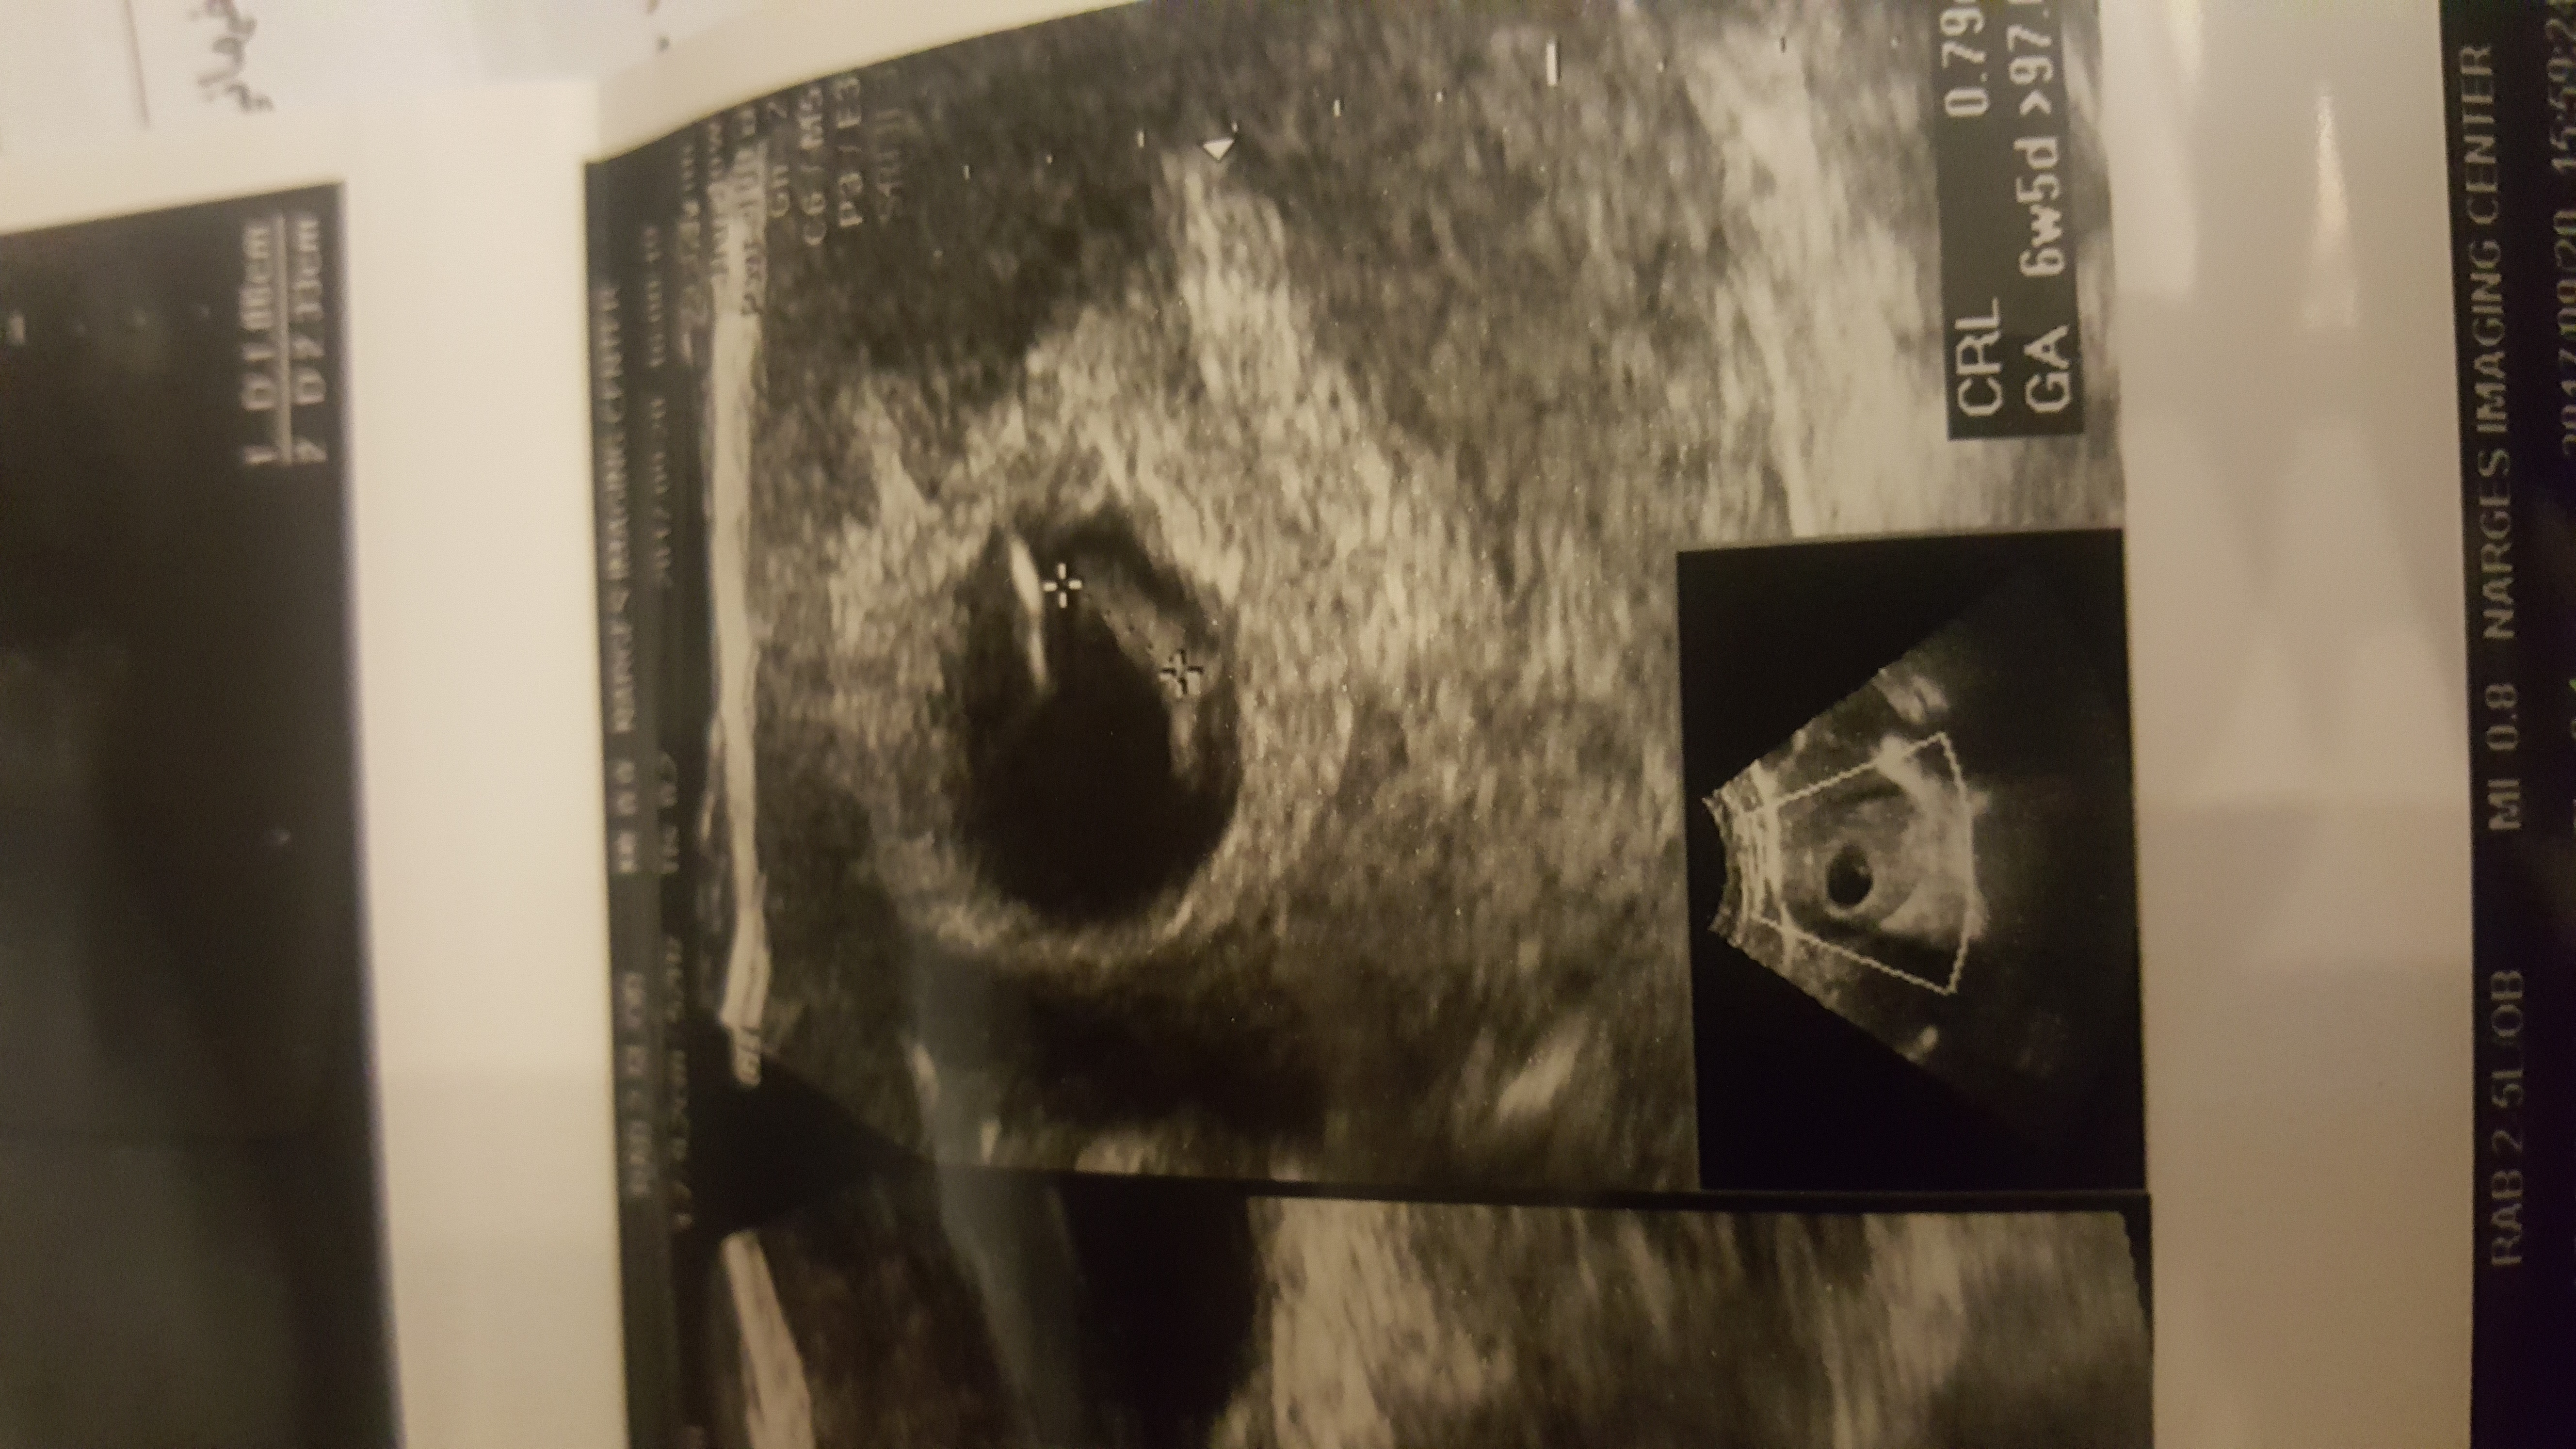

ببین عکسمو بچرخون ...چرخید تو گذاشتن ... این عکس ساک حاملگیمه تو هفته ۷ ... ببین جنین یا همون چیزی که قراره جنین بشه سمت چپ پایینه ... چپ پایین خود ساک ... نه رحم ... یعنی ممکنه دختر سمت راست رحم هم باشه یا پسر چپ رحم ... ولی اون جوجوی تو ساک باید ببینیم متمایل به چپه ساکه یا راست ساک حاملگی